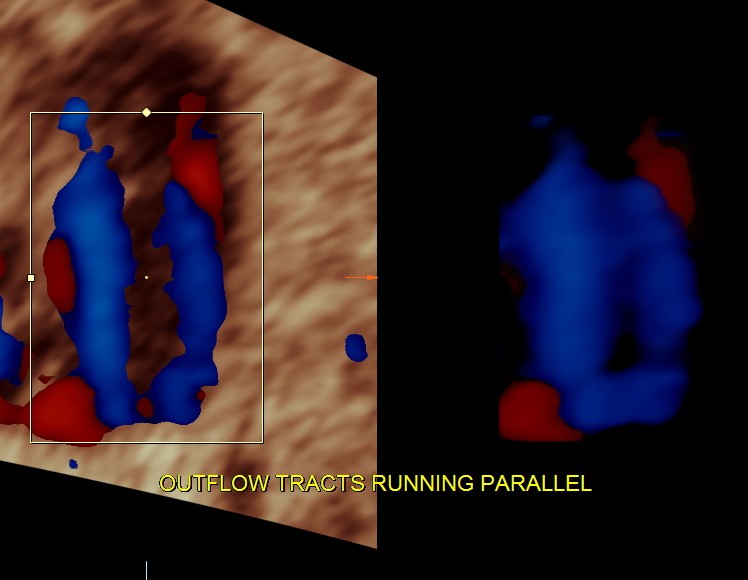

the following 3 D reconstructed image shows the parallel flow of the great arteries

THE DIAGNOSIS OFFERED WAS TRANSPOSITION OF GREAT ARTERIES WITH VENTRICULAR SEPTAL DEFECT